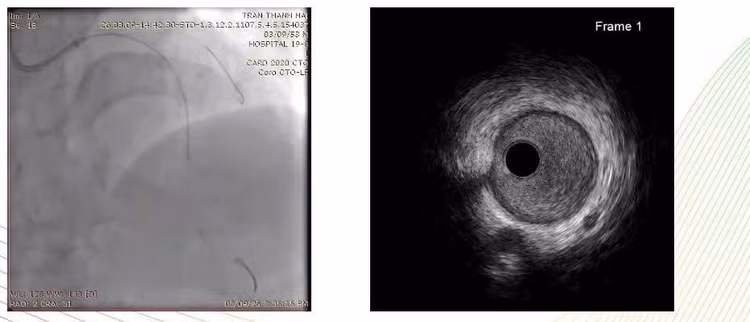

Kết quả chụp động mạch vành cho thấy tổn thương vôi hóa rất nặng, hẹp khít nhiều đoạn của hệ động mạch vành, với SYNTAX score 26.

Đánh giá tổn thương bằng IVUS, Siêu âm trong lòng mạch (IVUS) cho thấy: Vôi hóa gần như chu vi toàn bộ lòng mạch; Lòng mạch hẹp khít.

Đây là dạng tổn thương đặc biệt khó trong can thiệp mạch vành, vì stent rất khó nở nếu không xử lý tốt mảng vôi hóa trước.